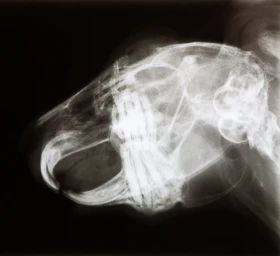

Striktně býložravé druhy drobných savců chované jako domácí mazlíčci, mezi které patří například králíci, morčata, činčily a osmáci, jsou velmi často...

Stomatologie drobných savců je rychle se rozvíjejícím odvětvím veterinární medicíny. V posledních letech stoupá obliba chovu drobných savců jako domác...